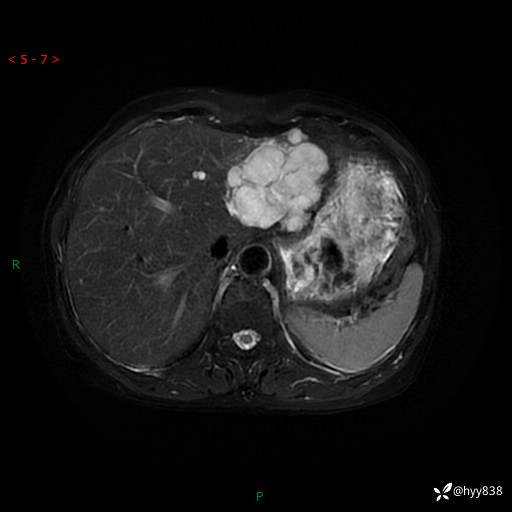

肝脏MRI平扫(同反相位)

T2WIfs+DWI

增强(动脉期+静脉期+延迟期)